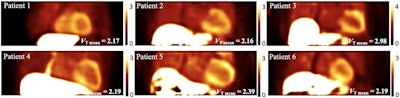

In an effort to determine the optimal method for quantifying F-18 flutemetamol myocardial uptake, the researchers performed kinetic modeling on dynamic PET scans of six ATTR cardiac amyloidosis patients. After dynamic images were reconstructed, the team then tested several compartmental models and analyzed parametric images of the volume of distribution.

A two-tissue reversible compartment model was the winner. The simplified graphical Logan plot identified the volume of distribution parameter generated from the first 30-minute dynamic scan was a quantitative parameter deemed by the researchers to be potentially useful for diagnosing and evaluating treatment in patients with ATTR cardiac amyloidosis.